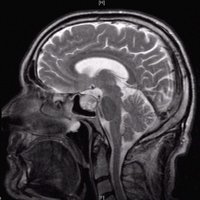

Hypophysenadenom

Hypophysenadenom T2 sagittal